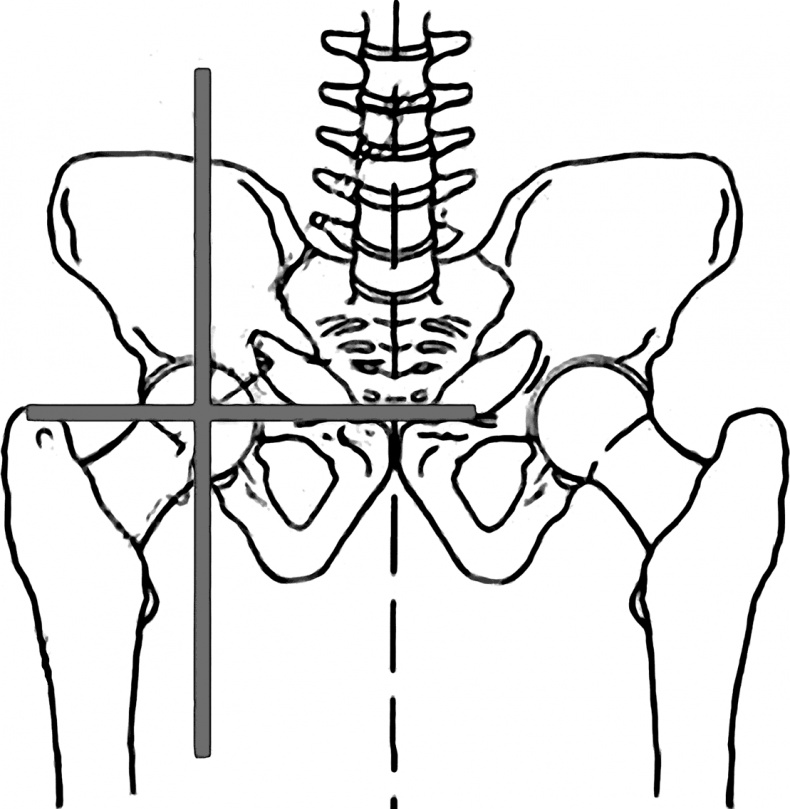

Человек ходит по Земле ногами и «питается» от нее теллурическими токами, заряжаясь электрической и магнитной активностью. Поэтому одна нога у него «плюс», а другая «минус». Соответственно, наши конечности имеют не только разный знак, но и разный вектор направления: одна нога (как и рука) притягивается к земле, а другая отталкивается, одна нога имеет направление вглубь тела, а другая – во внешнее пространство – тело идет на разрыв. И минимальный уровень такого дисбаланса неизбежен, поскольку обеспечивает необходимую разность потенциалов. Начальное равновесие тела зависит от положения тазобедренных суставов. Их симметрия обеспечивает баланс всей «ракеты». Иначе она не «полетит». В идеале вертикальная ось по фронтальной поверхности тела должна проходить строго между ногами, по срединной линии тела и переносице. Симметрию тазовых суставов во фронтальной плоскости (на виде спереди) можно увидеть на рис. 15. ![]() Рис. 15. Симметрия тазовых суставов А теперь сравните его с рис. 16 – горизонталь, идущая по ним, перекашивается к левой ноге. ![]() Рис. 16. Асимметрия таза Видно, что уровень левой стороны (реальной стороны человека) ниже, чем правой. Значит, левая нога больше опирается на землю. Именно здесь нас поджидает дисбаланс под названием «опорная нога». На опорную ногу при ходьбе приходится бо́льшая часть веса человека. И потому биомеханический рисунок тела соответствует рисунку «хиазма», который был известен еще античным скульптурам (рис. 17). ![]() Рис. 17. Хиазм на теле человека Он изображался стоящей фигурой человека, у которого тяжесть тела перенесена на опорную ногу. Поднявшемуся из-за этого бедру соответствует опущенное плечо, а другому, опущенному бедру – поднятое плечо. По законам физики любое действие вызывает противодействие, приводя к рождению компенсационных сил: чем сильнее мы опираемся на землю, тем сильнее она выталкивает опорную ногу, укорачивая ее и буквально затягивая вглубь таза. И все определяется работой «нейтральной зоны» системы левитации, находящейся в районе грудобрюшной диафрагмы, разделяющей тело на две ступени. Именно она, одновременно, и разъединяет, и соединяет обе половины тела невидимой связью. Когда зона левитации, где встречаются противоположные заряды, перестает работать, электромагнитный баланс нарушается. В случае усиления дисбаланса (рис. 18) укороченная левая нога начинает сильнее притягиваться к земле (серая стрелочка). В силу возникновения сил противодействия она начинает выталкиваться (черная стрелочка) и по диагонали выталкивать правое плечо. ![]() Рис. 18. Направления деформаций при синдроме «опорная нога» Выявить подобную асимметрию можно не только по уровню ягодиц, но главное и по уровню талии и бедер – в данном примере правый бок будет выше левого. В своей норме такие деформации свойственны «условно здоровому» человеку и практически не проявляются в теле. Как только система левитации закрывается, эти деформации начинают увеличиваться и приводить к сколиозам, ротациям и наклонам тела. Поэтому общая статика всегда определяется компенсационными реакциями тела на свое «заваливание» на опорную ногу в попытках удержать равновесие. Одним из главных требований к балансу тазовой области является симметрия крестца по срединной линии, делящей спину на две половинки. Если крестец смещен к левой или правой ягодице, начинаются сколиотические и ротационные подвижки позвоночника. Поэтому первое, чем занимается остеопат, – выставляет крестец строго по центру. Простыми приемами Осьмионики его можно выправить и самостоятельно. Главное, потом контролировать свою позу при сидении на стуле – не сидеть на одной ягодице, заваливая тело, не закидывать ногу за ногу, а держать тело ровно по центру промежности и ягодиц. Та же эталонная ось, идущая в саггитальной плоскости, должна идти по профилю тела человека через несколько ключевых точек: центр пятки, шарнир тазобедренного сустава, акромиальный отросток плеча (его головку) и центр наружного слухового прохода. Я назвала эту ось Гравитационной вертикалью (рис. 19). ![]() Рис. 19. Гравитационная вертикаль В физике она называется мировой осью или осью мира. Поэтому основной прием на осанку и носит название Ось мира. От нее и пошло название методики – Осьмионика (сходство с фамилией автора – случайность). Чтобы понять, как должно быть выстроено тело по Гравитационной вертикали, обратимся опять к строению ракеты. Ведь если она не будет стоять вертикально по отношению к Земле, она не взлетит. Вы считаете, что сравнение тела человека с ракетой некорректно, потому что ракеты летают вертикально, а мы передвигаемся по земле горизонтально? Действительно, все современные ракеты взлетают вертикально. Однако первая ракета, предложенная Циолковским, основоположником нашей авиации, делала разбег по земле и лишь потом взмывала в воздух. Свой труд «Космические ракетные поезда» К. Э. Циолковский опубликовал в 1929 году. И, не считая горизонтального взлета, все современные ракеты вобрали в себя основные принципы многоступенчатой ракеты Циолковского. Многоступенчатость ракеты – это в первую очередь рациональное использование ресурсов, экономия топлива. Точно так же происходит в нашем теле: его конструкция в виде трехступенчатой ракеты позволяет нам экономить силы, которые Природа дала нам на всю жизнь. Если проанализировать принцип работы каждой ступени ракеты, вы обнаружите большое сходство между ними и телом человека. В реальной ракете разделение первой и второй ступени происходит за счет взрыва между ними, благодаря чему сбрасывается нижняя первая ступень. У человека такой взрыв осуществляется благодаря процессам, идущим в желудочно-кишечном тракте (ЖКТ). По мнению исследователей, в тонком кишечнике происходит холодный термоядерный синтез, обеспечивающий обменные процессы. |